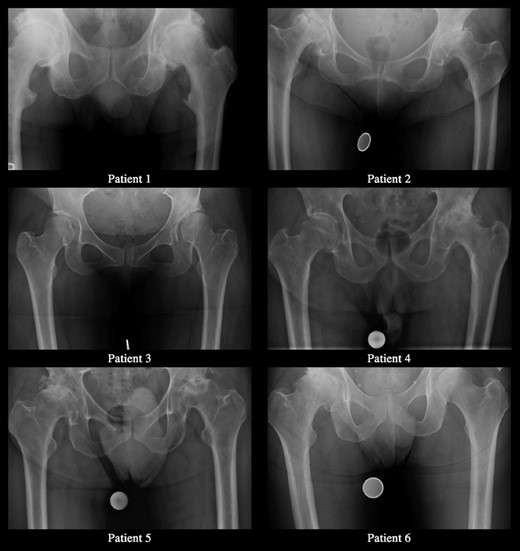

All patients underwent a DAA THA complicated by immediate post-operative femoral nerve palsy. Clinical characteristics are summarized in Table 1. Preoperative radiographs are exhibited in Fig. 1.

The proposed etiology for neuropathy after THA includes direct trauma, excessive tension during extremity lengthening, direct contact with methylmethacrylate or the heat of its polymerization, constriction by wire fixation, femoral component dislocation, ischemia, and compression; however, in most patients the actual cause has not been determined [1, 4, 6]. Weale et al. [7] hypothesized that anterior retractors placed around the acetabulum were responsible for subclinical damage to the femoral nerve. As the femoral nerve passes distal to the inguinal ligament, it is in close proximity to the anterior wall of the acetabulum, traveling on average 1.8–2.2 cm from the anterior lip [3, 8]. With only the iliopsoas between the anterior capsule and the femoral nerve, any retractor misplacement or repositioning places the nerve at risk of compression directly or by proxy if the retractor is placed through the iliopsoas bulk. All six of our patients had multiple, large, anterior osteophytes as evidenced by preoperative radiographs in Fig. 1, which we believe may have contributed to difficulty attaining or maintaining direct contact between the anterior retractor and the wall of the anterior acetabulum, putting the femoral nerve at risk.